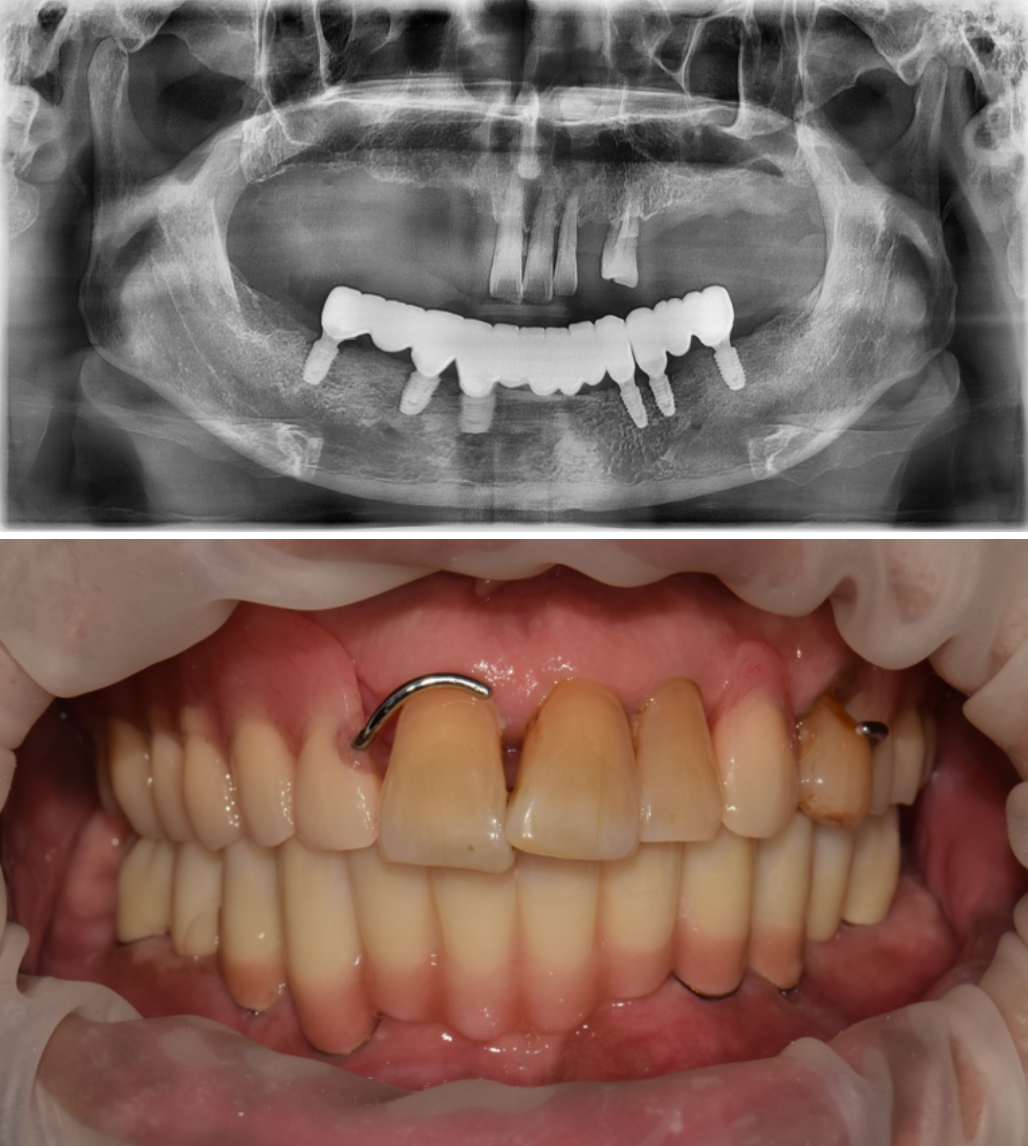

통증이 두려워서 무절개로 수술을 하고 싶어요. 무절개 임플란트 수술을 문의 주셨던 환자분입니다. 윗턱에는 불편하지만 사용하시던 틀니가 있기에, 일단은 아랫턱만 임플란트 수술을 원하셨습니다. 촬영일시 : 2024.05.14. 초진 내원 당시 구강내 엑스레이 사진입니다. 보시다시피 아랫턱은 완전 무치악으로 치아가 전혀없습니다. 무절개 방식을 사용하여군더더기 손 동작 없이 정확하고 빠르게 15분만에 수술을 마무리 해드렸습니다ㅎㅎ 충분한 숙련도를 갖춘 의료진이라면 불필요한 디지털 가이드 방식의 수술이나 복잡하고 번거로운 도구없이 감각만으로 빠르고 정확한 수술이 가능합니다. 지금까지 만 개 이상의 임플란트를 식립해오면서 얻게 된 수술 경험으로 불필요한 과정없이 필요한 술식만으로 임플란트 수술을 진행하고 있습니다. 촬영일시 : 2024.05.14. 수술 직후 3차원 CT입니다. 정확한 위치에 올바른 각도와 간격으로 임플란트들이 가지런히 식립되어있습니다. 촬영일시 : 2024.08.22. 4개월 후 완성 후 사진입니다. 지금까지 365일 늘 가까운 서울대학교 치과병원을 지향하는, 365서울앞선치과 강동우 대표원장이었습니다! 앞으로도 도움이 되는 증례로 찾아뵙겠습니다. 감사합니다. [ 치료기간: 2024년 5월14일 ~2025년 8월 22일 )] |